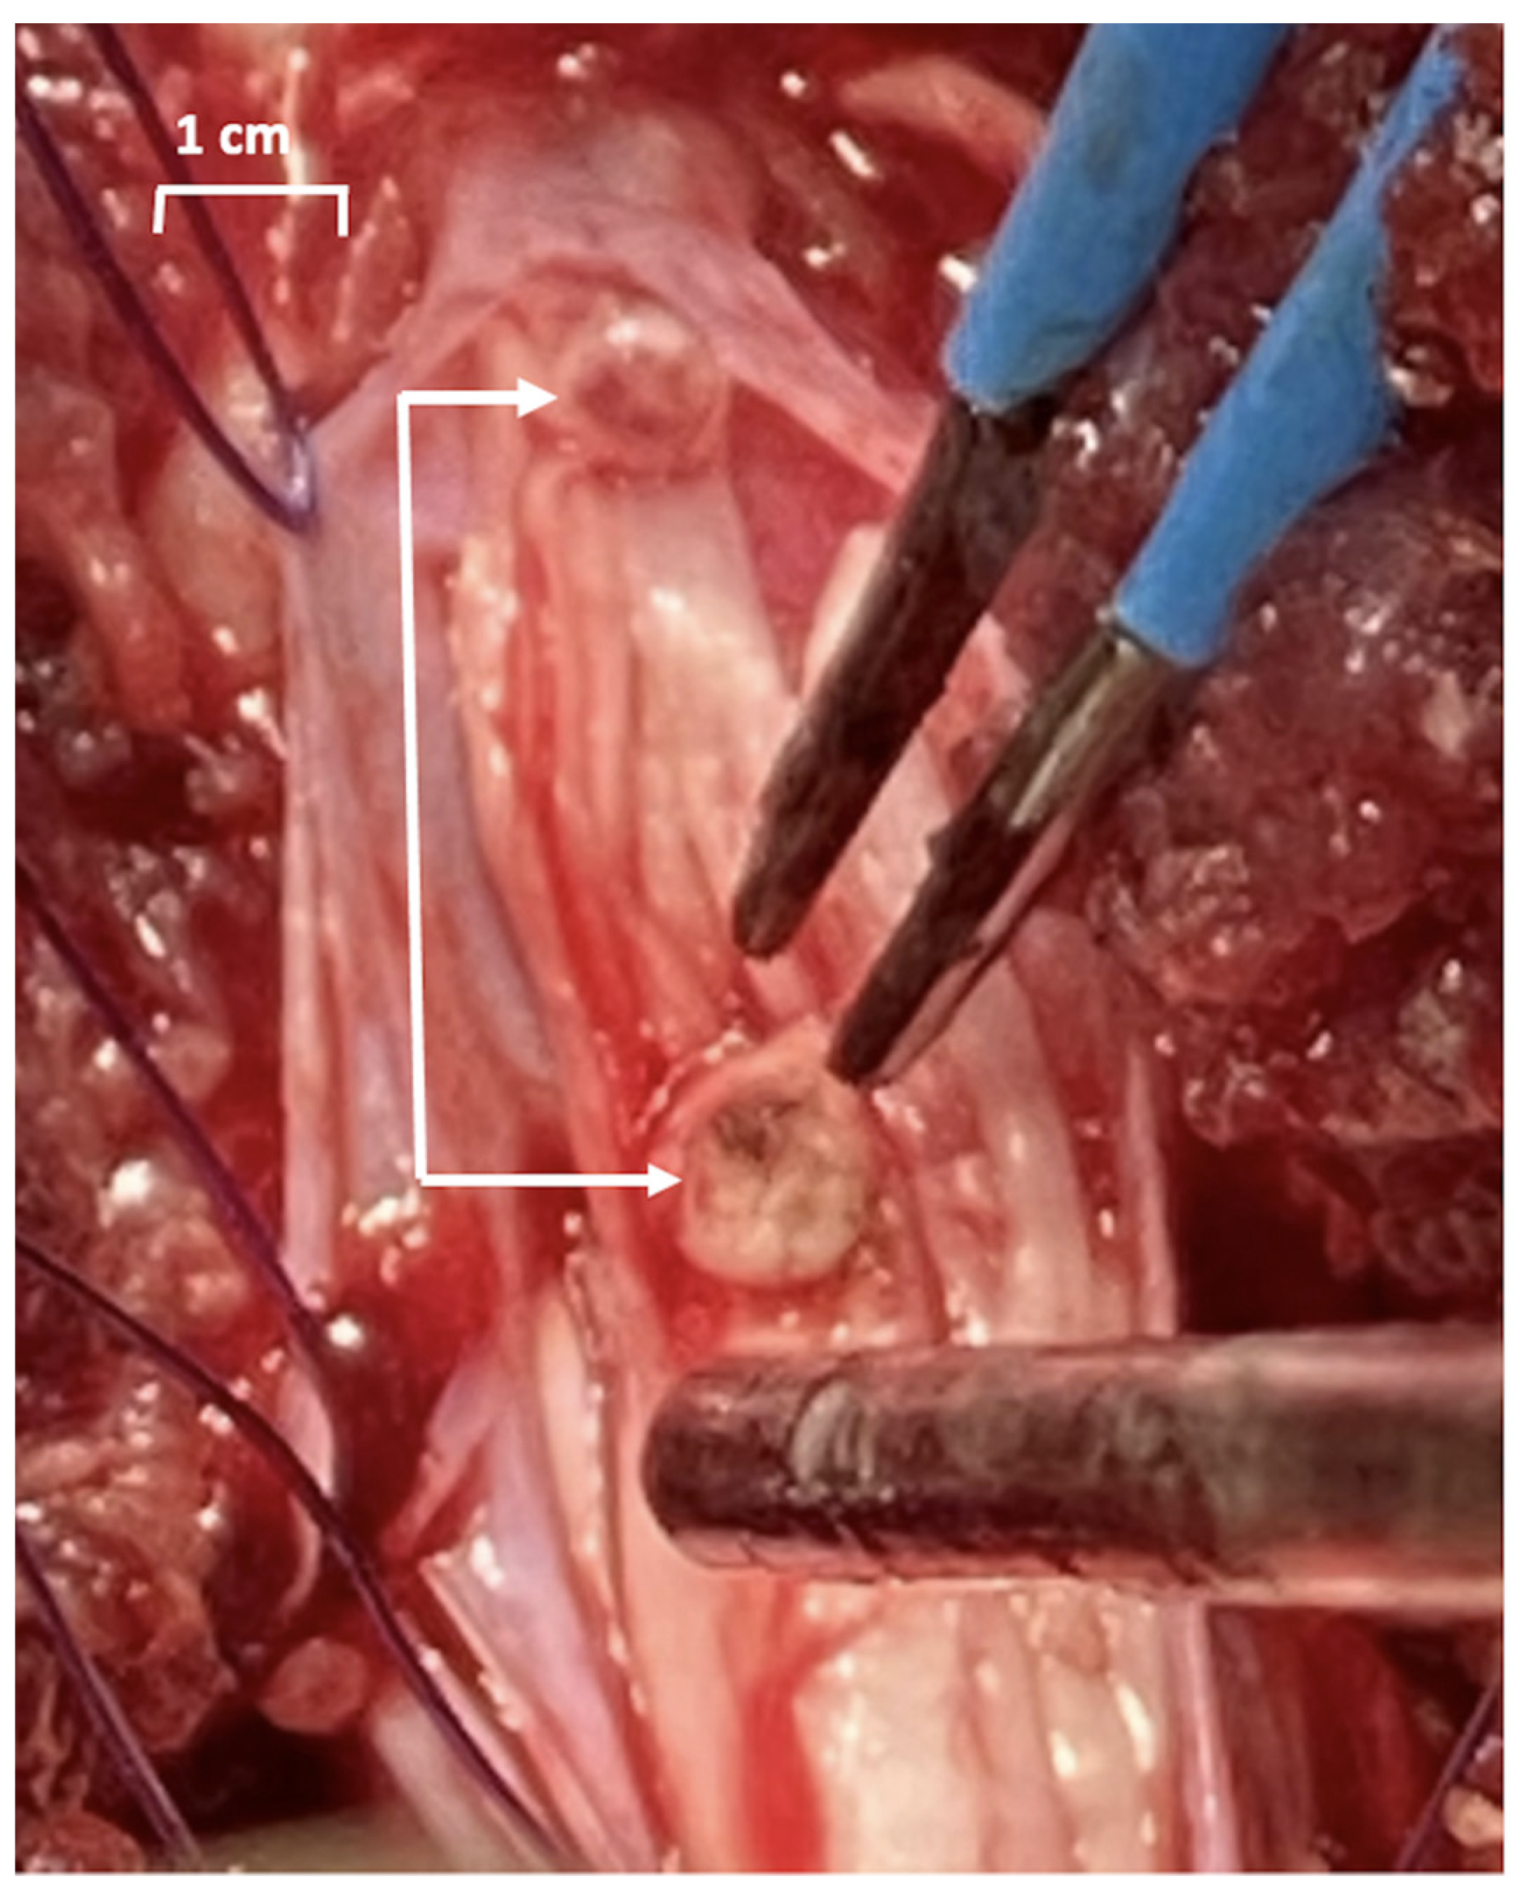

Figure 2.

Photograph of the sacral spinal lesion during surgery. The sectioned part of the sacral levels of lesion are marked with arrows. The cauterizing electrodes (blue) and a suction tube are also shown.